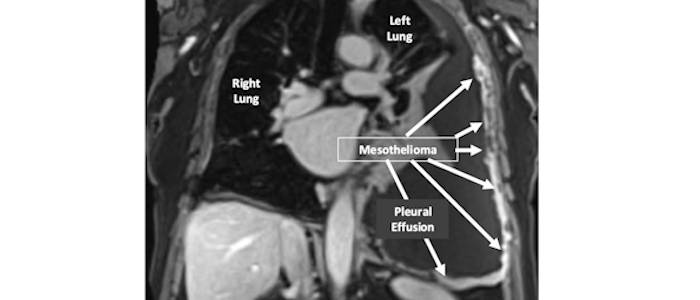

Definition and Validation of mesothelioma endotypes associatedwith treatment response and resistance based on multi-omic PREDICT-Meso data